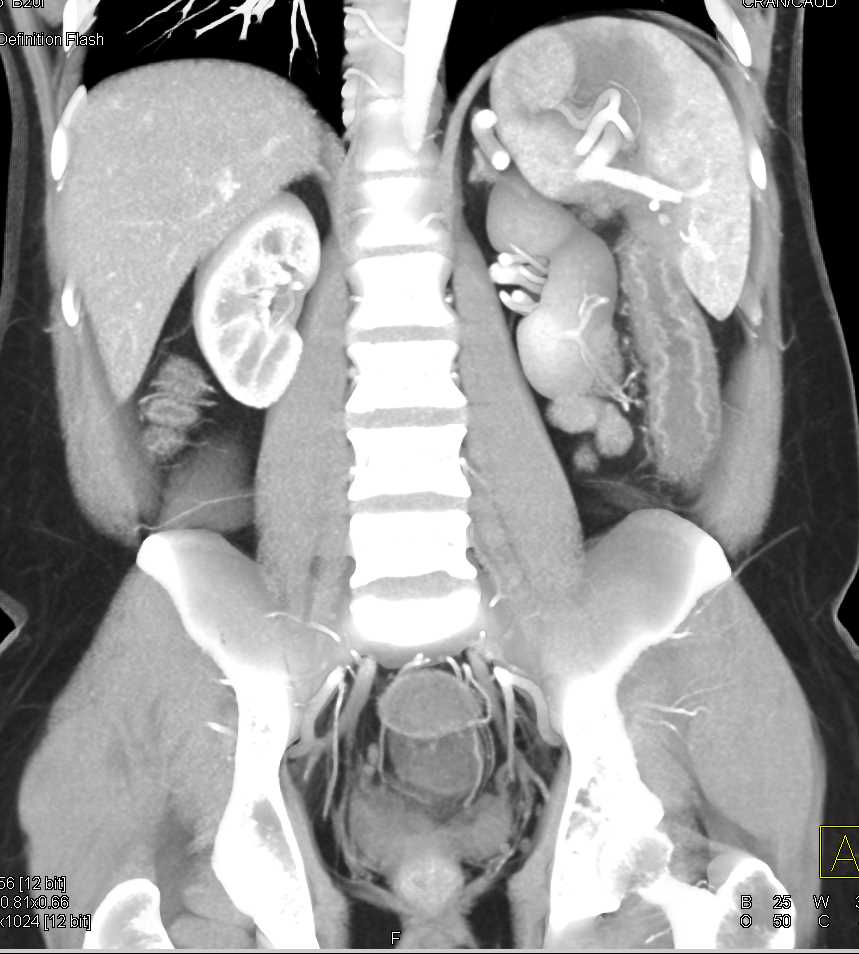

Diverticular Disease